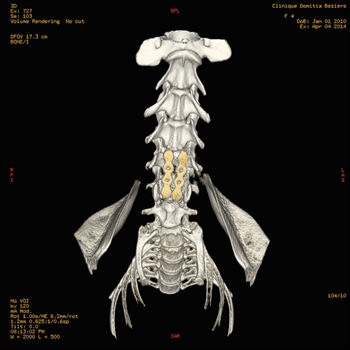

Le Scanner ou Tomodensitométrie Numérisée.

Depuis quelques années, le développement du scanner en médecine vétérinaire (imagerie par tomodensitométrie numérisée) s'est fortement accéléré avec la multiplication des structures équipées.

Le scanner est actuellement l'examen de choix pour le diagnostic des hernies discales chez les carnivores domestiques et d'une façon générale pour l'exploration des pathologies du rachis. Ses capacités de dessuperposition des structures anatomiques et sa meilleure résolution spatiale lui permettent, avec les machines de dernière génération, de supplanter définitivement les examens radiologiques sous contraste.

Le scanner permet à la fois une meilleure approche de l'étage de la lésion, mais aussi une meilleure latéralisation de celle-ci, ce qui est capital en cas de geste chirurgical. Il permet aussi, en cas de hernies multiples (ce qui est fréquent dans certaines races comme le Bouledogue français) d'avoir une approche lésionnelle permettant, au travers de critères objectifs, de faire un tri entre les hernies pour isoler celle responsable des symptômes nerveux.

L'examen tomodensitométrie du rachis se fait avant et après injection de produit de contraste iodé pour rehausser les lésions. Dans certains cas extrêmes, et au demeurant rarissimes, une injection complémentaire de produit de contraste dans l'espace sous arachnoïdien peut être nécessaire, l'examen réalisé alors se nomme un myéloscanner. Cet examen peut s'avérer très utile, notamment pour le diagnostic de certaines affections rares des méninges nommées kystes arachnoïdiens, présentes en particulier chez le Rottweiler, et dont le diagnostic constitue une des limites du scanner avec le syndrome de Chiari.

Coupes axiales

Scanner d'une Hernie discale T13L1 extrusive chez un chien reformatages sagittal et coronale